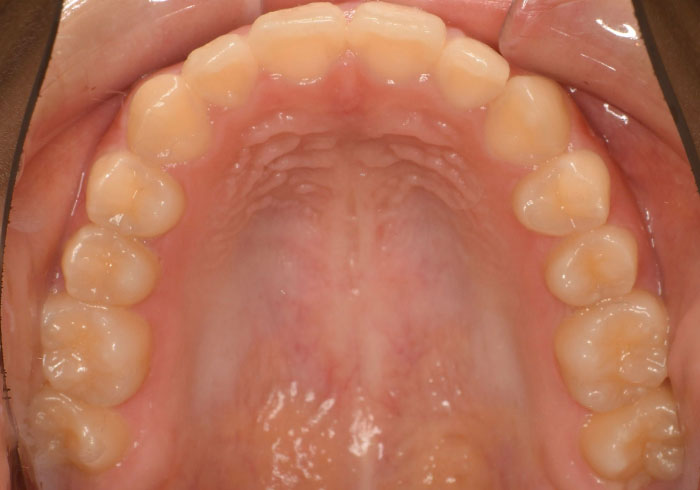

治療前

マウスピース矯正 マウスピース矯正 マウスピース矯正